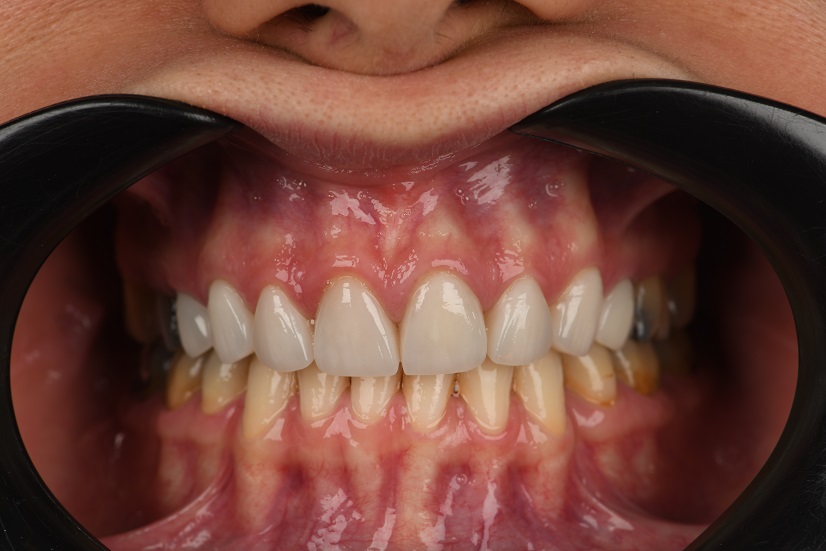

یکی از بیماران ما با لمینیت‌های قدیمی و فرسوده مراجعه کردند که ظاهر طبیعی و کیفیت اولیه خود را از دست داده بود. پس از مشاوره و بررسی دقیق، تصمیم به برداشتن لمینیت‌های قبلی و جایگزینی آن‌ها با 8 واحد لمینیت سرامیکی به رنگ طبیعی گرفتیم.

در ابتدا، لمینیت‌های قدیمی به دقت و بدون آسیب به دندان‌های طبیعی بیمار برداشته شد. سپس، با استفاده از تکنیک‌های پیشرفته و مواد باکیفیت، لمینیت‌های جدید طراحی و روی دندان‌های بیمار نصب شدند.

قبل درمان